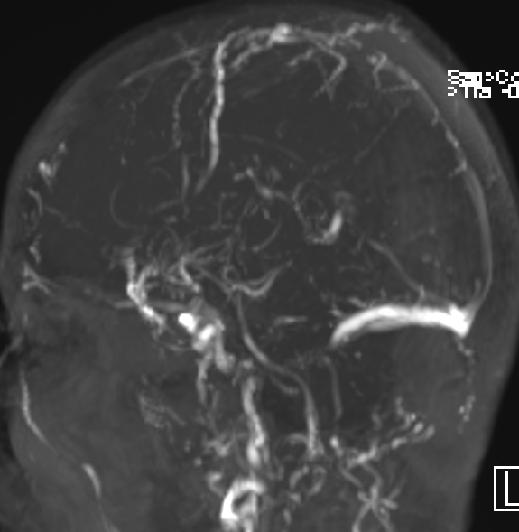

2015-1-30 DSA

脑压为60mm水柱

低颅压原因?(分流泵故障?脑顺应性差?

2015-2-1

在局麻下行腰椎穿刺术+ 测脑压术,患者取左侧卧位,测量脑脊液压力为60mm水柱。